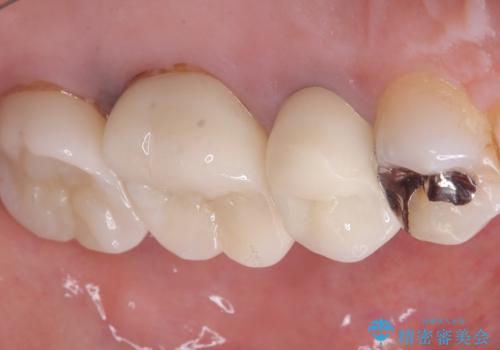

- 主訴:いつも物が詰まる場所があり気になる。衛生士に被せものと土台の境目に汚れが溜まっている箇所があると指摘され気になっている。

過去に入れた被せものと土台の歯との適合が悪く、隙間が出来ておりそこに汚れが溜まりやすい状態になっていました。セラミッククラウンでのやり替えとなりました。

唇側マージン不適なこと説明し、審美性・適合性に優れたセラミッククラウン(スタンダード)でのやり替えとなりました。